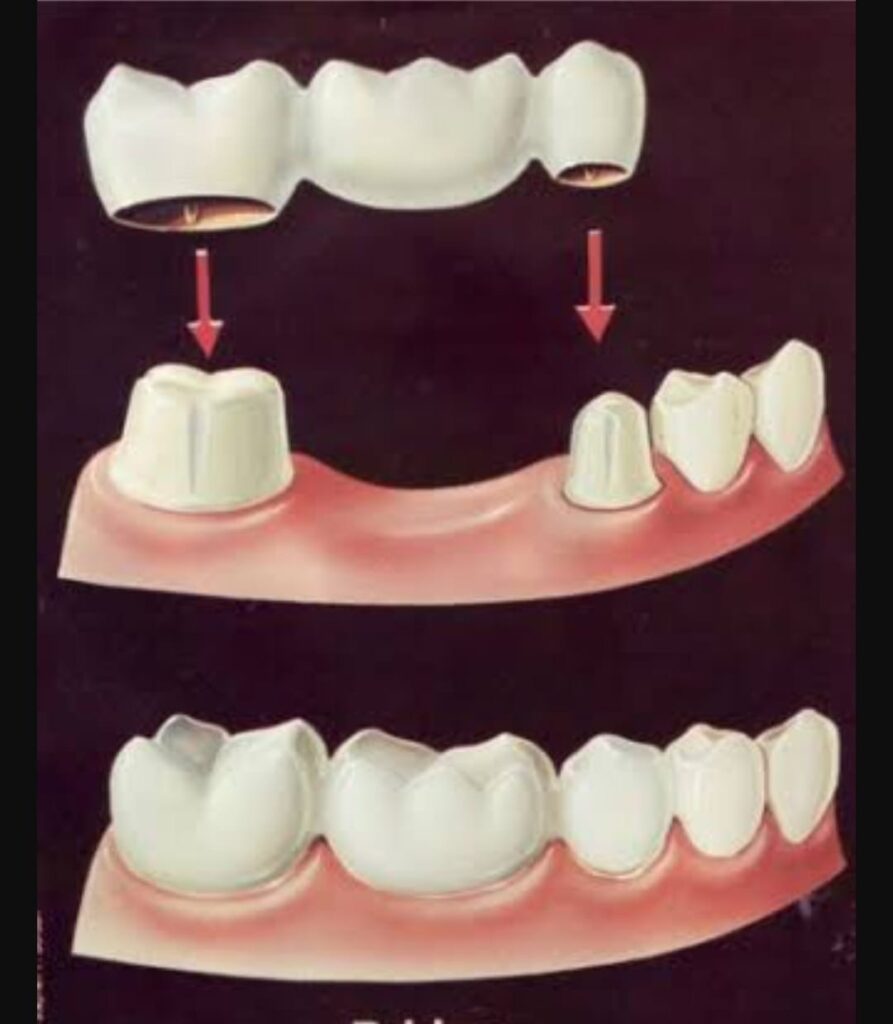

Fix and removal teeth

Fixing and removing teeth involves repairing damaged teeth or extracting those that are beyond repair. This process aims to restore oral function and prevent further dental issues.